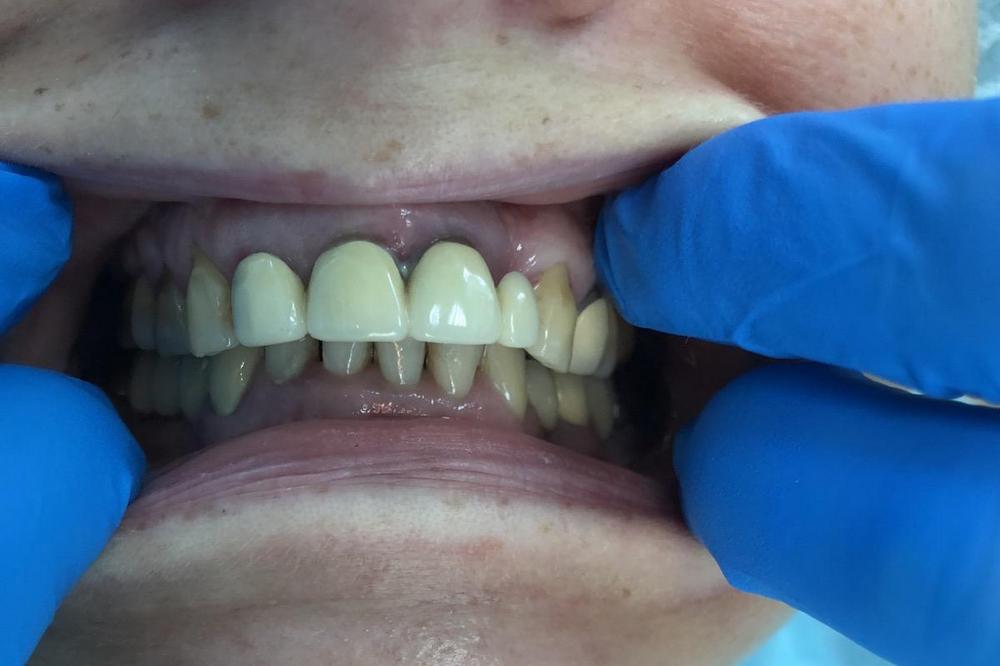

Изучив данные 3D-исследования, которые пациентка прислала через интернет, доктор предложил провести протезирование верхней и нижней челюстей в кратчайшие сроки при помощи методики All-on-6 (все на 6-ти). Во время операции были удалены старые протезы, оставшиеся зубы, установлены 6 имплантатов на верхней и 6 имплантатов на нижних челюстях, и за 5 дней были изготовлены и фиксированы несъемные эстетичные протезы на обеих челюстях.

Пациентка осталась очень довольна результатом.